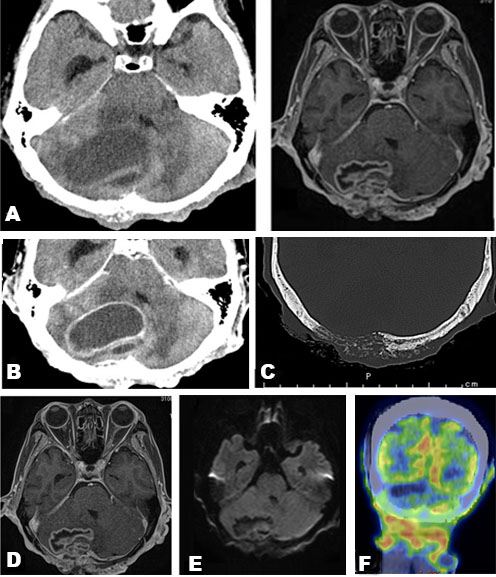

Blood examination showed elevated C-reactive protein levels. Computed tomography (CT) revealed a mass in the right cerebellum, obstructing the fourth ventricle and causing acute hydrocephalus (Figure 2A). On the bone window, the occipital bone had osteolytic change beneath the skin lesion (Figure 2C). The lesion had an enhanced cystic appearance on the contrast CT (Figure 2B). We suspected of brain abscess of the cerebellum caused by soft tissue infection. Emergency cyst drainage was performed. The aspirated fluid was serous and the microbiological examination was negative. Gadolinium-enhanced magnetic resonance imaging (MRI) was performed after the operation. Magnetic resonance imaging results showed shrinkage of the cyst, and the decreased mass effect improved the occlusive hydrocephalus (Figure 2D). There were no findings that indicated brain abscess on diffusion-weighted image (DWI) (Figure 2E). We performed an 18F-fluorodeoxyglucose positron emission tomography (FDG-PET) CT scan to examine potential differential diagnoses, such as metastatic brain tumor or primary brain tumor. There was no uptake of FDG in the body or the cyst, suggesting an absence of primary cancer of the body. Instead, there was uptake on the occipital, nuchal skin (Figure 2F), and on the right side of the 12th thoracic vertebrae. Based on these findings, we suspected a skin tumor, and consulted dermatology. A punch biopsy of the occipital scalp was performed. Histologically, proliferation of tumor cells similar to basal cells is typically observed from the epidermis to the dermis. In the basal layer of the tumor, there was a gap between the palisading arrangement and surrounding connective tissue, mixed with melanocytes. Diverse and solid, lace-like proliferative images, and keratinized vesicles were also observed (Figure 3A and Figure 3B). Based on the histological findings, the diagnosis was BCC.

Figure 2: (A) CT demonstrated a cystic hypodense lesion in the posterior fossa. (B) Contrast enhanced CT revealed an enhanced cyst (55 × 30 × 40 mm). (C) Bone window showed osteolytic destruction on the occipital bone. (D) Postoperative contrast-enhanced MRI demonstrated a smaller enhanced cyst. (E) DWI showed an absence of high intensity in the lesion. (F) FDG uptake occurred in the occipital scalp erosion (Coronal).